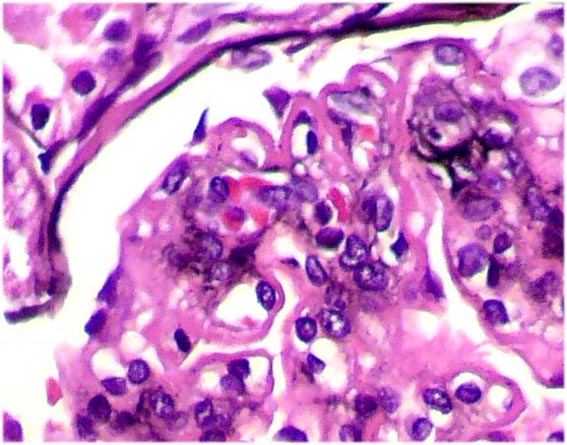

Figura 2.

H&E, X400.

Figura 3.